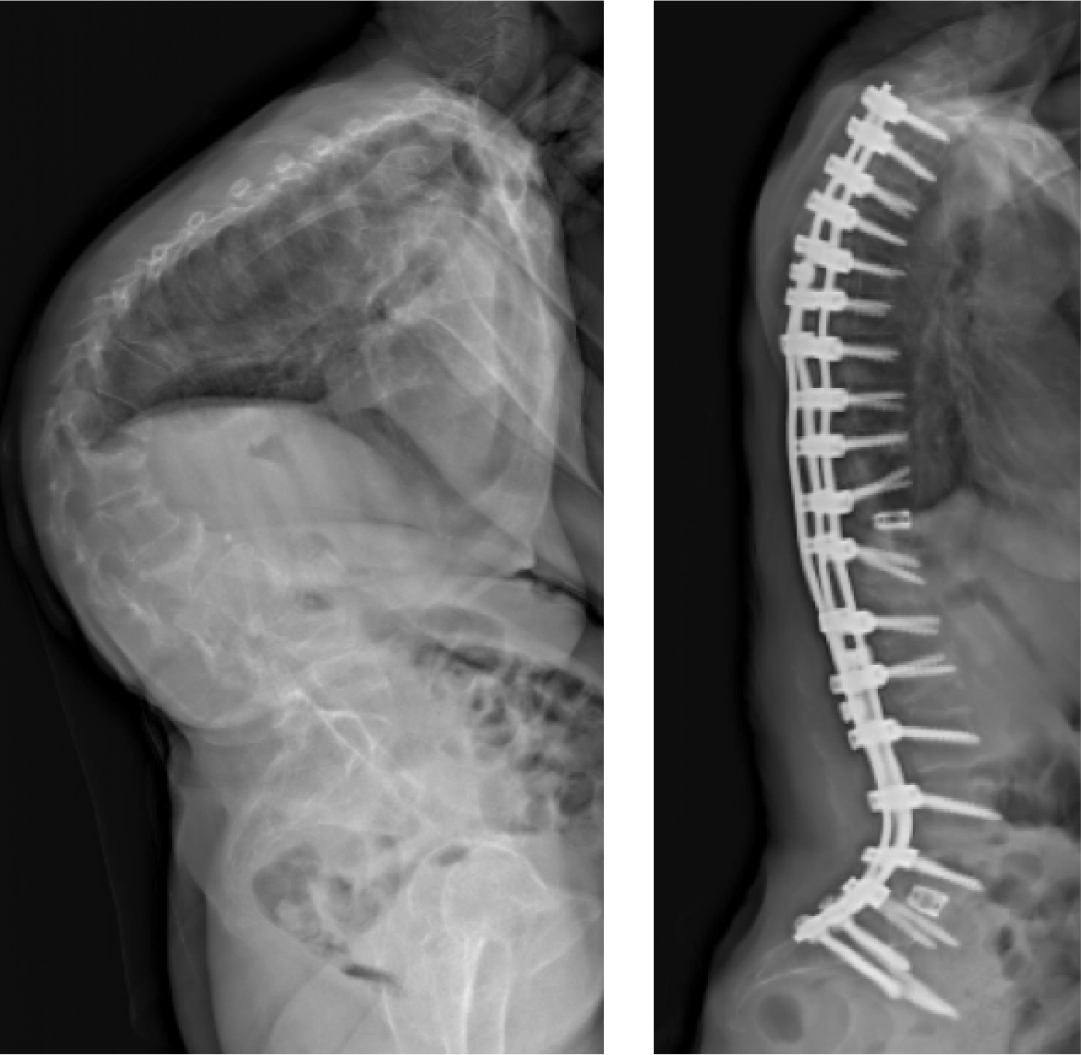

After meeting eight surgeons who could not treat her severe scoliosis, Patricia almost gave up hope of living without pain. But, the team at NewYork-Presbyterian didn’t hesitate—they performed reconstruction and fusion to straighten her spine and heal her nerves, giving her the hope that nobody else could.